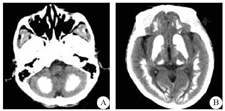

患者女性,46岁,因"肢体不灵活7年,加重伴记忆力下降1年"在2016年4月28日收治于遵义医学院附属医院神经内科。患者2009年无明显诱因被家属发现步态异常,不影响生活,未予重视,无特殊处理;2015年上述症状加重,伴记忆力下降、吐词欠清晰及姿势异常,不能胜任工作,于我院就诊,予药物治疗,症状无明显好转。2016年3月4日就诊于我科门诊行头颅CT示双侧大小脑多发钙化灶(图1),查甲状旁腺激素、甲状腺功能无异常,甲状腺球蛋白抗体:997.9 IU/mL(正常值为0~115 IU/mL)。患者为明确诊断复诊于重庆医科大学附属第一医院,复查头颅CT结果同我院,电解质及降钙素无异常(排除甲状旁腺减退症及假性甲状旁腺减退症)。患者既往体健,近期未患感冒。患者父亲75岁时出现记忆力下降、肢体活动障碍,未行相关检查,78岁时因肺部疾病去世。入院体检:心肺腹查体无明显异常,甲状腺轻度增大,双手掌指关节以远皮肤粗糙、泛红、皮温异常(图2),全身未见皮脂腺纤维素瘤及牛奶咖啡斑(排除结节性硬化症),双足内收、背伸畸形。入院神经系统体检:吐词欠清晰,记忆力下降,左侧轻度面舌瘫,双上肢肌力5-级,双下肢肌力4+级,四肢肌张力稍增高,右侧Oppenheim征、Pussep征、Chaddock征均阳性,余无明显阳性体征。入院后查双上肢血管超声提示双侧尺动脉管径偏细,左侧流速减低,右侧锁骨下动脉内中膜增厚。诊断"Fahr病"。予抗胆碱能及健脑药物等对症支持治疗。

A:双侧小脑半球对称性钙化灶;B:双侧额颞枕叶、基底节区、背侧丘脑对称性钙化灶